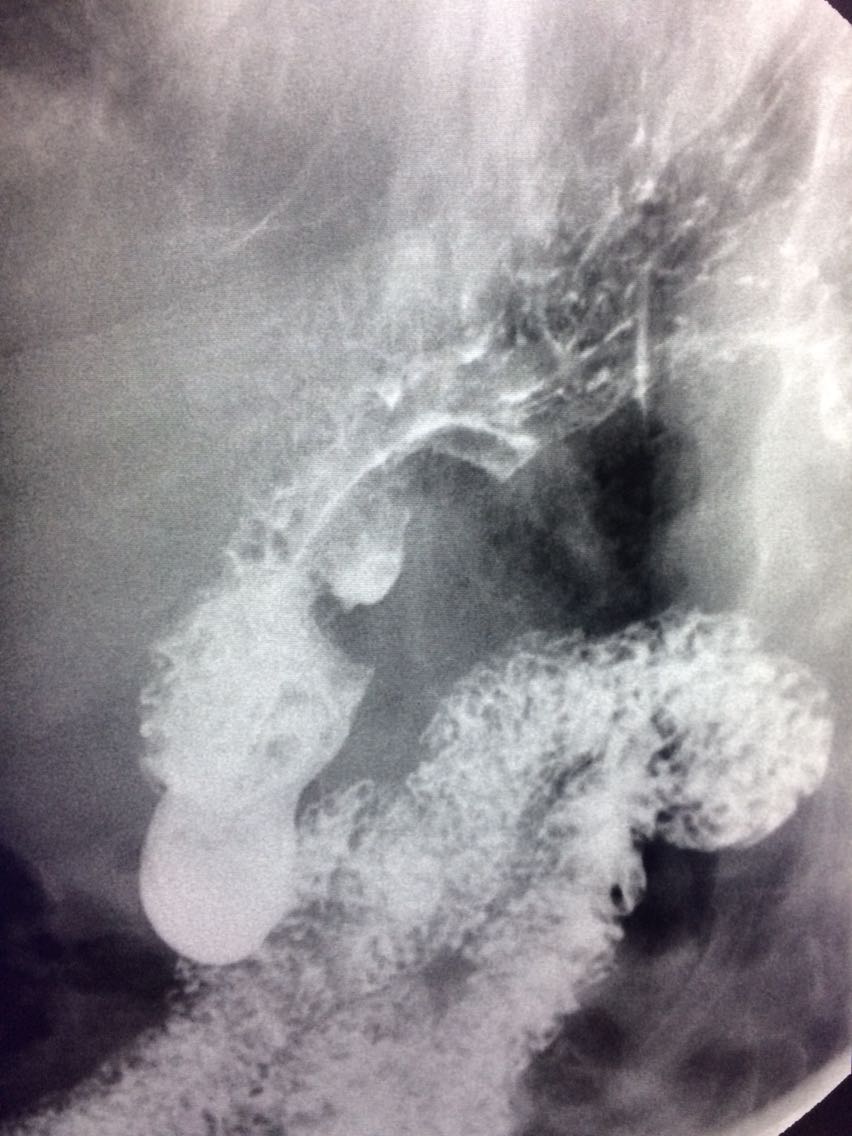

一例溃疡型胃癌。

男,45岁 反复胃疼5年余。 5年来,反复出现胃疼,进食后半小时加重,经常感觉饥饿,当地按胃溃疡,给予阿莫西林,奥美拉唑治疗,具体不详,效果欠佳,遂入院,入院来,饮食睡眠,二便可。 既往体健。 入院上消化道造影如图。

讨论,诊断及鉴别诊断? 胃溃疡的影像表现? 溃疡良恶性的鉴别? 入院后行胃大部切除术。 诊断,胃腺癌。